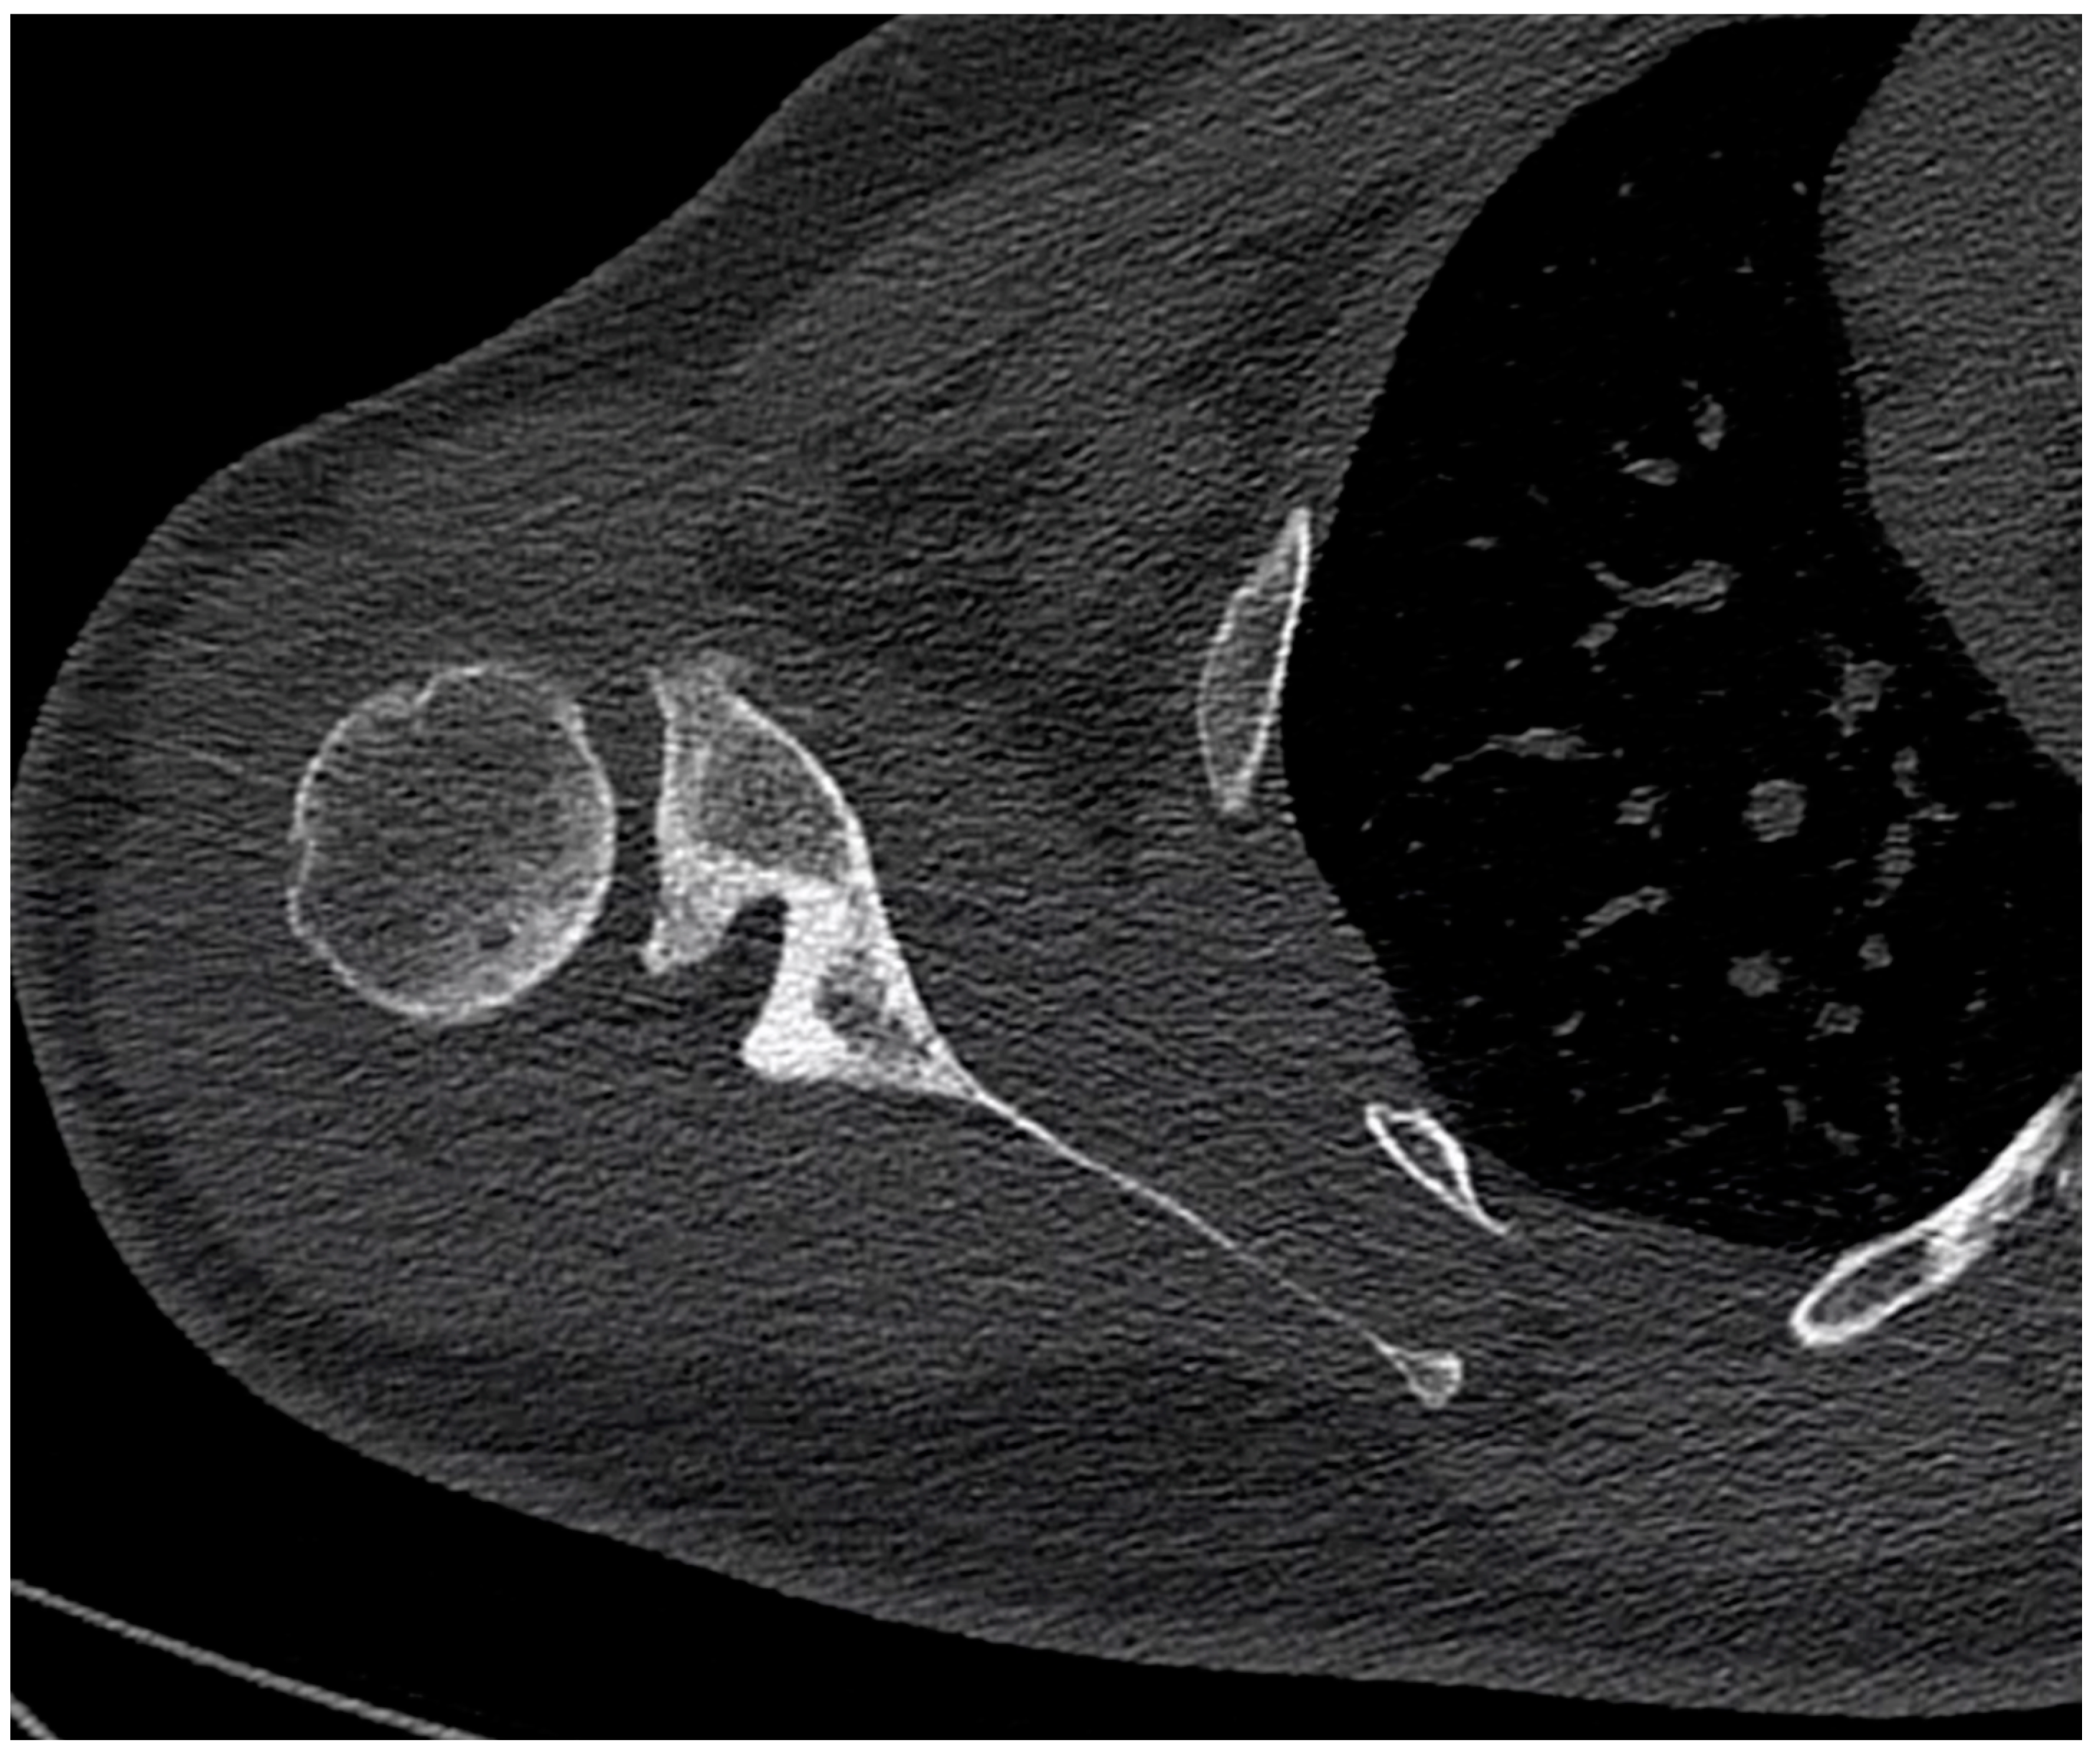

2.5. Scapula Positioning Relative to the Thorax

| At the trigonum spinae region | 77.7 ± 10.7 | 74.2 | (62.9–95.7) | 74.6 ± 14.9 | 67.4 | (62.5–103.5) | 0.583 |

| At the inferior scapula angle region | 107.9 ± 12.3 | 108.7 | (82.1–119.6) | 102.1 ± 18.5 | 103.1 | (78.0–134.1) | 0.466 |